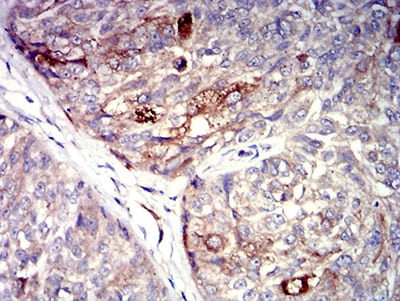

分类: 科研抗体货号: 31307别名: P2Y8应用: IHC,IF,FCM反应种属: Human